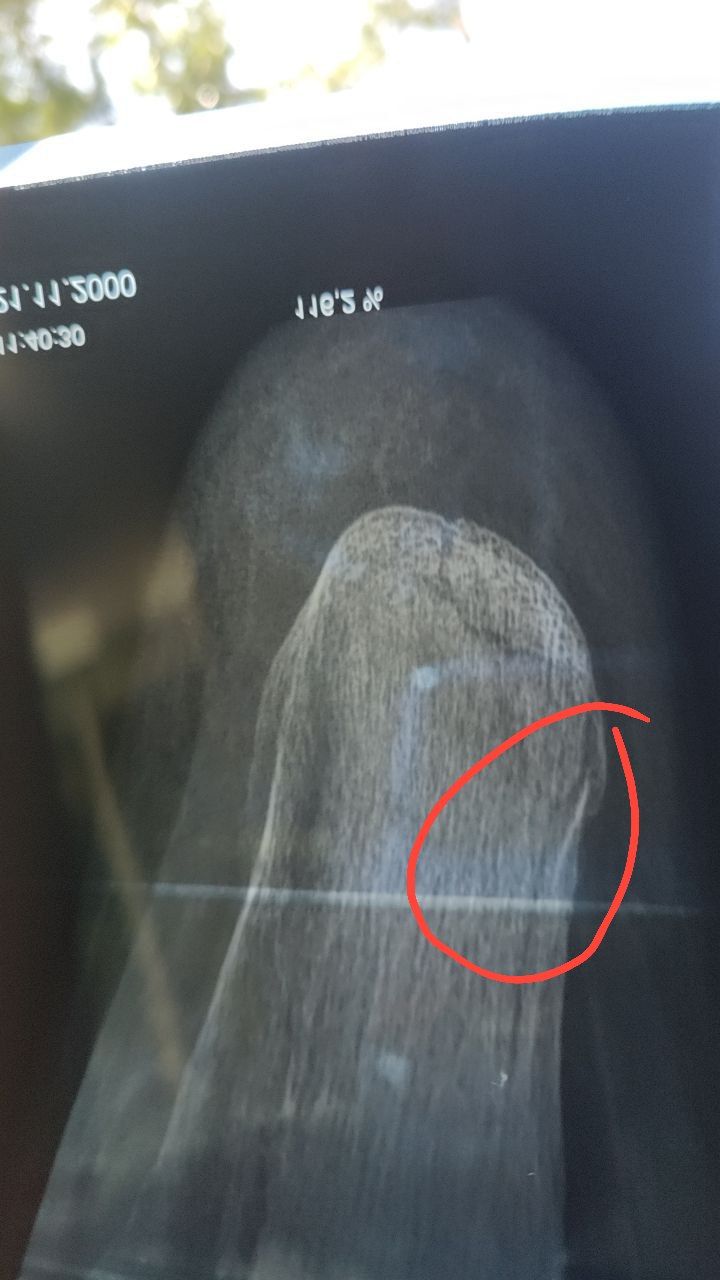

Перелом пяточной кости   2 ответа

Здравствуйте, через 30 дней после перелома сделали рентген снимок, который оказался намного детальней первого, я на нем увидел странность, а врач не дает четкого ответа, прикладываю снимок, посмотрите пожалуйста, нет ли второго перелома в правой части кости, сейчас врач сказал ходить в лангете еще 14 дней, после этого снять САМОМУ, без приема, и начать реабилитацию, пытаться наступить на ногу к 60 дню от перелома